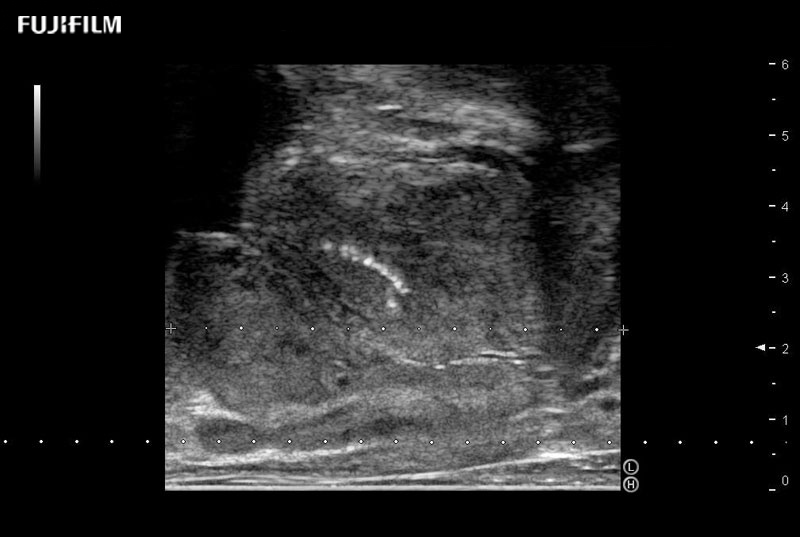

38mm footprint is ideal for scrotal and penile doppler imaging

Main Specifications:

Larger footprint is ideal for scrotal and penile doppler imaging